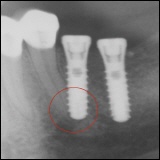

Fehlerhafte Positionierung der Implantate

Chronischen Entzündung um Implantate